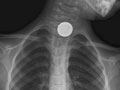

- Find foreign objects, such as coins or other small pieces of metal, in the tube to the stomach (esophagus), the airway, or the lungs. A chest X-ray may not be able to see food, nuts, or wood fibers.

- A foreign object is seen in the esophagus, breathing tubes, or lungs.